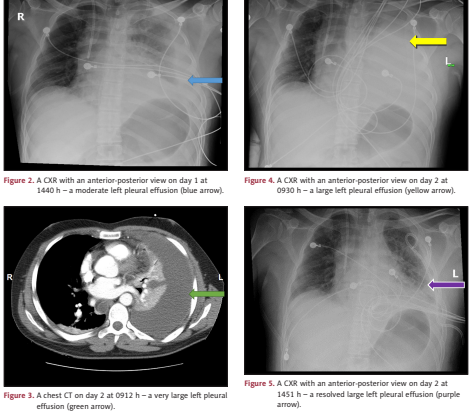

胸膜炎进展:第1天胸片显示中度左侧胸腔积液(图2)第2天CT证实大量左侧胸腔积液伴肺不张(图3),胸片示左肺近乎完全实变(图4)引流1.3L浑浊胸腔积液,符合渗出性胸液特征(LDH 9208 U/L,葡萄糖2 mg/dL)